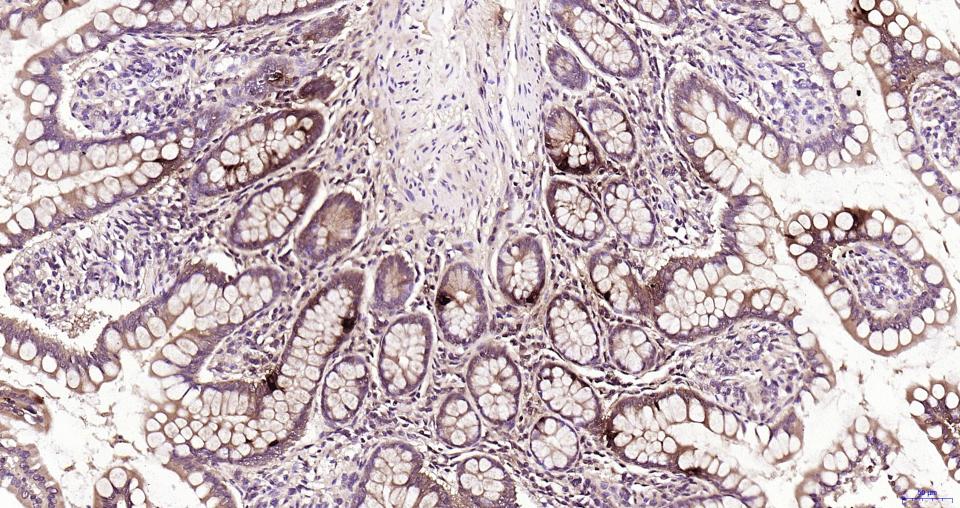

Paraformaldehyde-fixed, paraffin embedded Mouse colon; Antigen retrieval by boiling in sodium citrate buffer (pH6.0) for 15 min; Antibody incubation with Glucagon Monoclonal Antibody, Unconjugated(bsm-62053R) at 1:200 overnight at 4°C, followed by conjugation to the SP Kit(Rabbit, SP-0023) and DAB (C-0010) staining.

Paraformaldehyde-fixed, paraffin embedded Human colon; Antigen retrieval by boiling in sodium citrate buffer (pH6.0) for 15 min; Antibody incubation with Glucagon Monoclonal Antibody, Unconjugated(bsm-62053R) at 1:200 overnight at 4°C, followed by conjugation to the SP Kit(Rabbit, SP-0023) and DAB (C-0010) staining.

Paraformaldehyde-fixed, paraffin embedded Rat colon; Antigen retrieval by boiling in sodium citrate buffer (pH6.0) for 15 min; Antibody incubation with Glucagon Monoclonal Antibody, Unconjugated(bsm-62053R) at 1:200 overnight at 4°C, followed by conjugation to the SP Kit(Rabbit, SP-0023) and DAB (C-0010) staining.